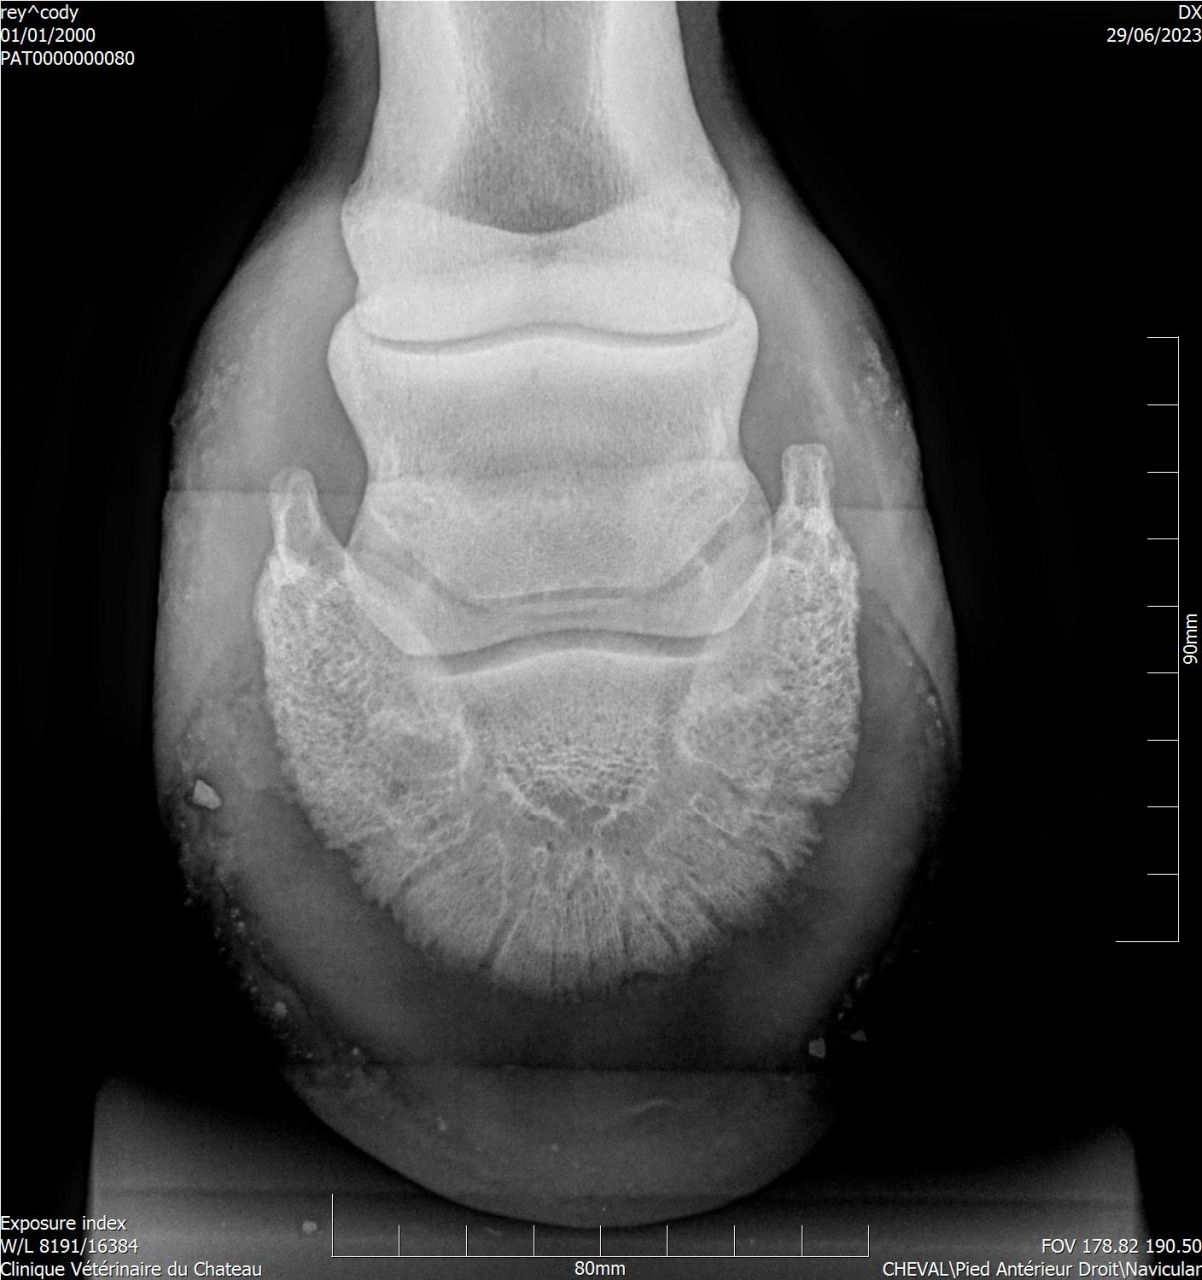

| Dire merci | Cody a une sensibilité que personne n'arrive à expliquer ... Les radios montrent une ossification des processus palmaires sur les 2 antérieurs, et une légère bascule de P3 sur l'antérieur gauche. A priori le naviculaire est correct. J'ai trouvé un maréchal-ferrant qui pose des Duplos. Vaut il mieux brocher ou coller ? |

| Dire merci | Deux personnes m'ont parlé des Duplo, les vétos ont conseillé ferrure en M ou ferrure normale ... L'année dernière Cody a été ferré avec des fers oignons et plaques en cuir, ça n'a rien changé. Ces fers ont été conseillés par le maréchal-ferrant car le véto consulté à l'époque conseillait des egg bar. Il me semble qu'avec l'ossification des processus palmaires les fers en métal n'étaient pas l'idéal. Voici les radios : ![]() ![]() ![]() ![]() J'essaye de régler les problèmes physiques pour voir si ça change quelque chose monté. Je commence par les pieds. |